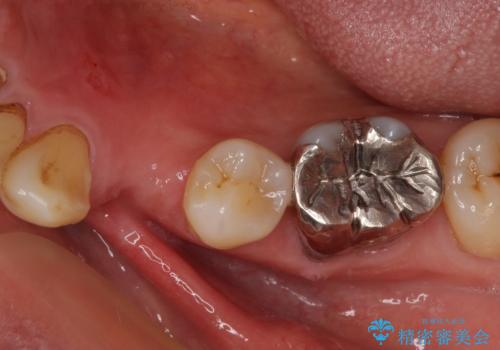

- 近医にて抜歯が必要と言われたとのことで来院された患者様です。

顕微鏡下で確認したところ、歯根に及ぶ破折線が認められたため、抜歯を行うこととしました。

インプラント治療をお勧めしましたが、取り扱いや手入れが煩雑でも良いとのことで、可撤性義歯(入れ歯)にて補綴治療を行うこととしました。